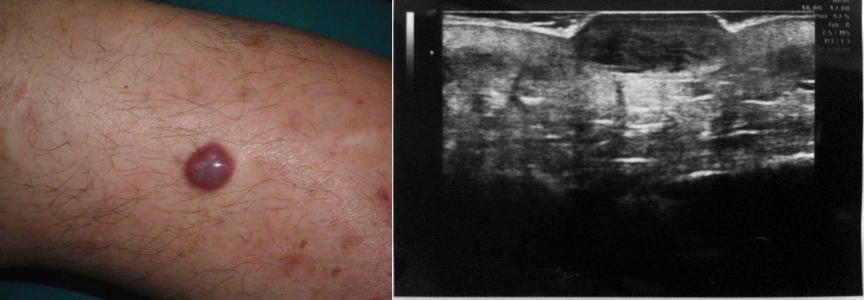

2. MALATTIE INFIAMMATORIE – Idrosadenite suppurativa

Ascesso : lesione fluida ipo/anecogena a limiti mal definiti che raggiunge gli strati profondi.